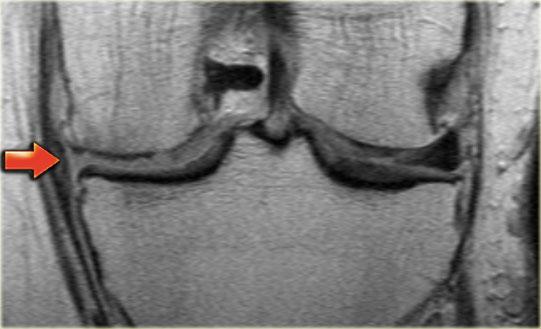

Ghi nhận một đường rách hướng tâm tại vị trí chân sụn chêm phía sau của sụn chêm trong, đường rách xuyên suốt toàn bộ chiều dày sụn chêm với hình ảnh khe dịch lan dọc theo khuyết tổn thương (mũi tên đỏ).

Rách chân sụn chêm thường đi kèm với hiện tượng thoát vị sụn chêm ra ngoài bờ mâm chày.

Thoát vị sụn chêm trên 3 mm thường liên quan đến các tổn thương rách tại vùng chân sụn chêm (6).

Trong trường hợp bên trái, ghi nhận một đường rách hướng tâm hoàn toàn tách rời sừng sau khỏi chân bám của nó (mũi tên đỏ).

Ngoài ra còn có hình ảnh thoát vị sụn chêm mức độ tối thiểu (hình 1/6).

Đây là một trường hợp rách chân sụn chêm trong khác.

Lưu ý rằng sừng sau không còn bám vào xương chày.

Thay vào đó, có thể thấy một khoảng hở (mũi tên cong).

Những tổn thương rách này rất dễ bị bỏ sót khi người đọc nhầm tưởng sừng sau vẫn bình thường.